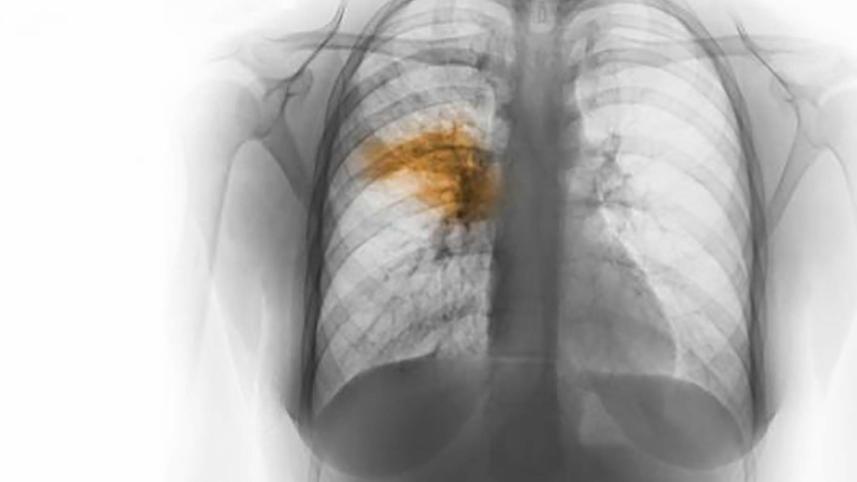

Pneumonia is a respiratory infection usually caused by a virus, bacteria or fungi.

The infection makes the lungs fill with fluid, making breathing difficult. On the other hand, a healthy child's lung fills with air when they breathe.